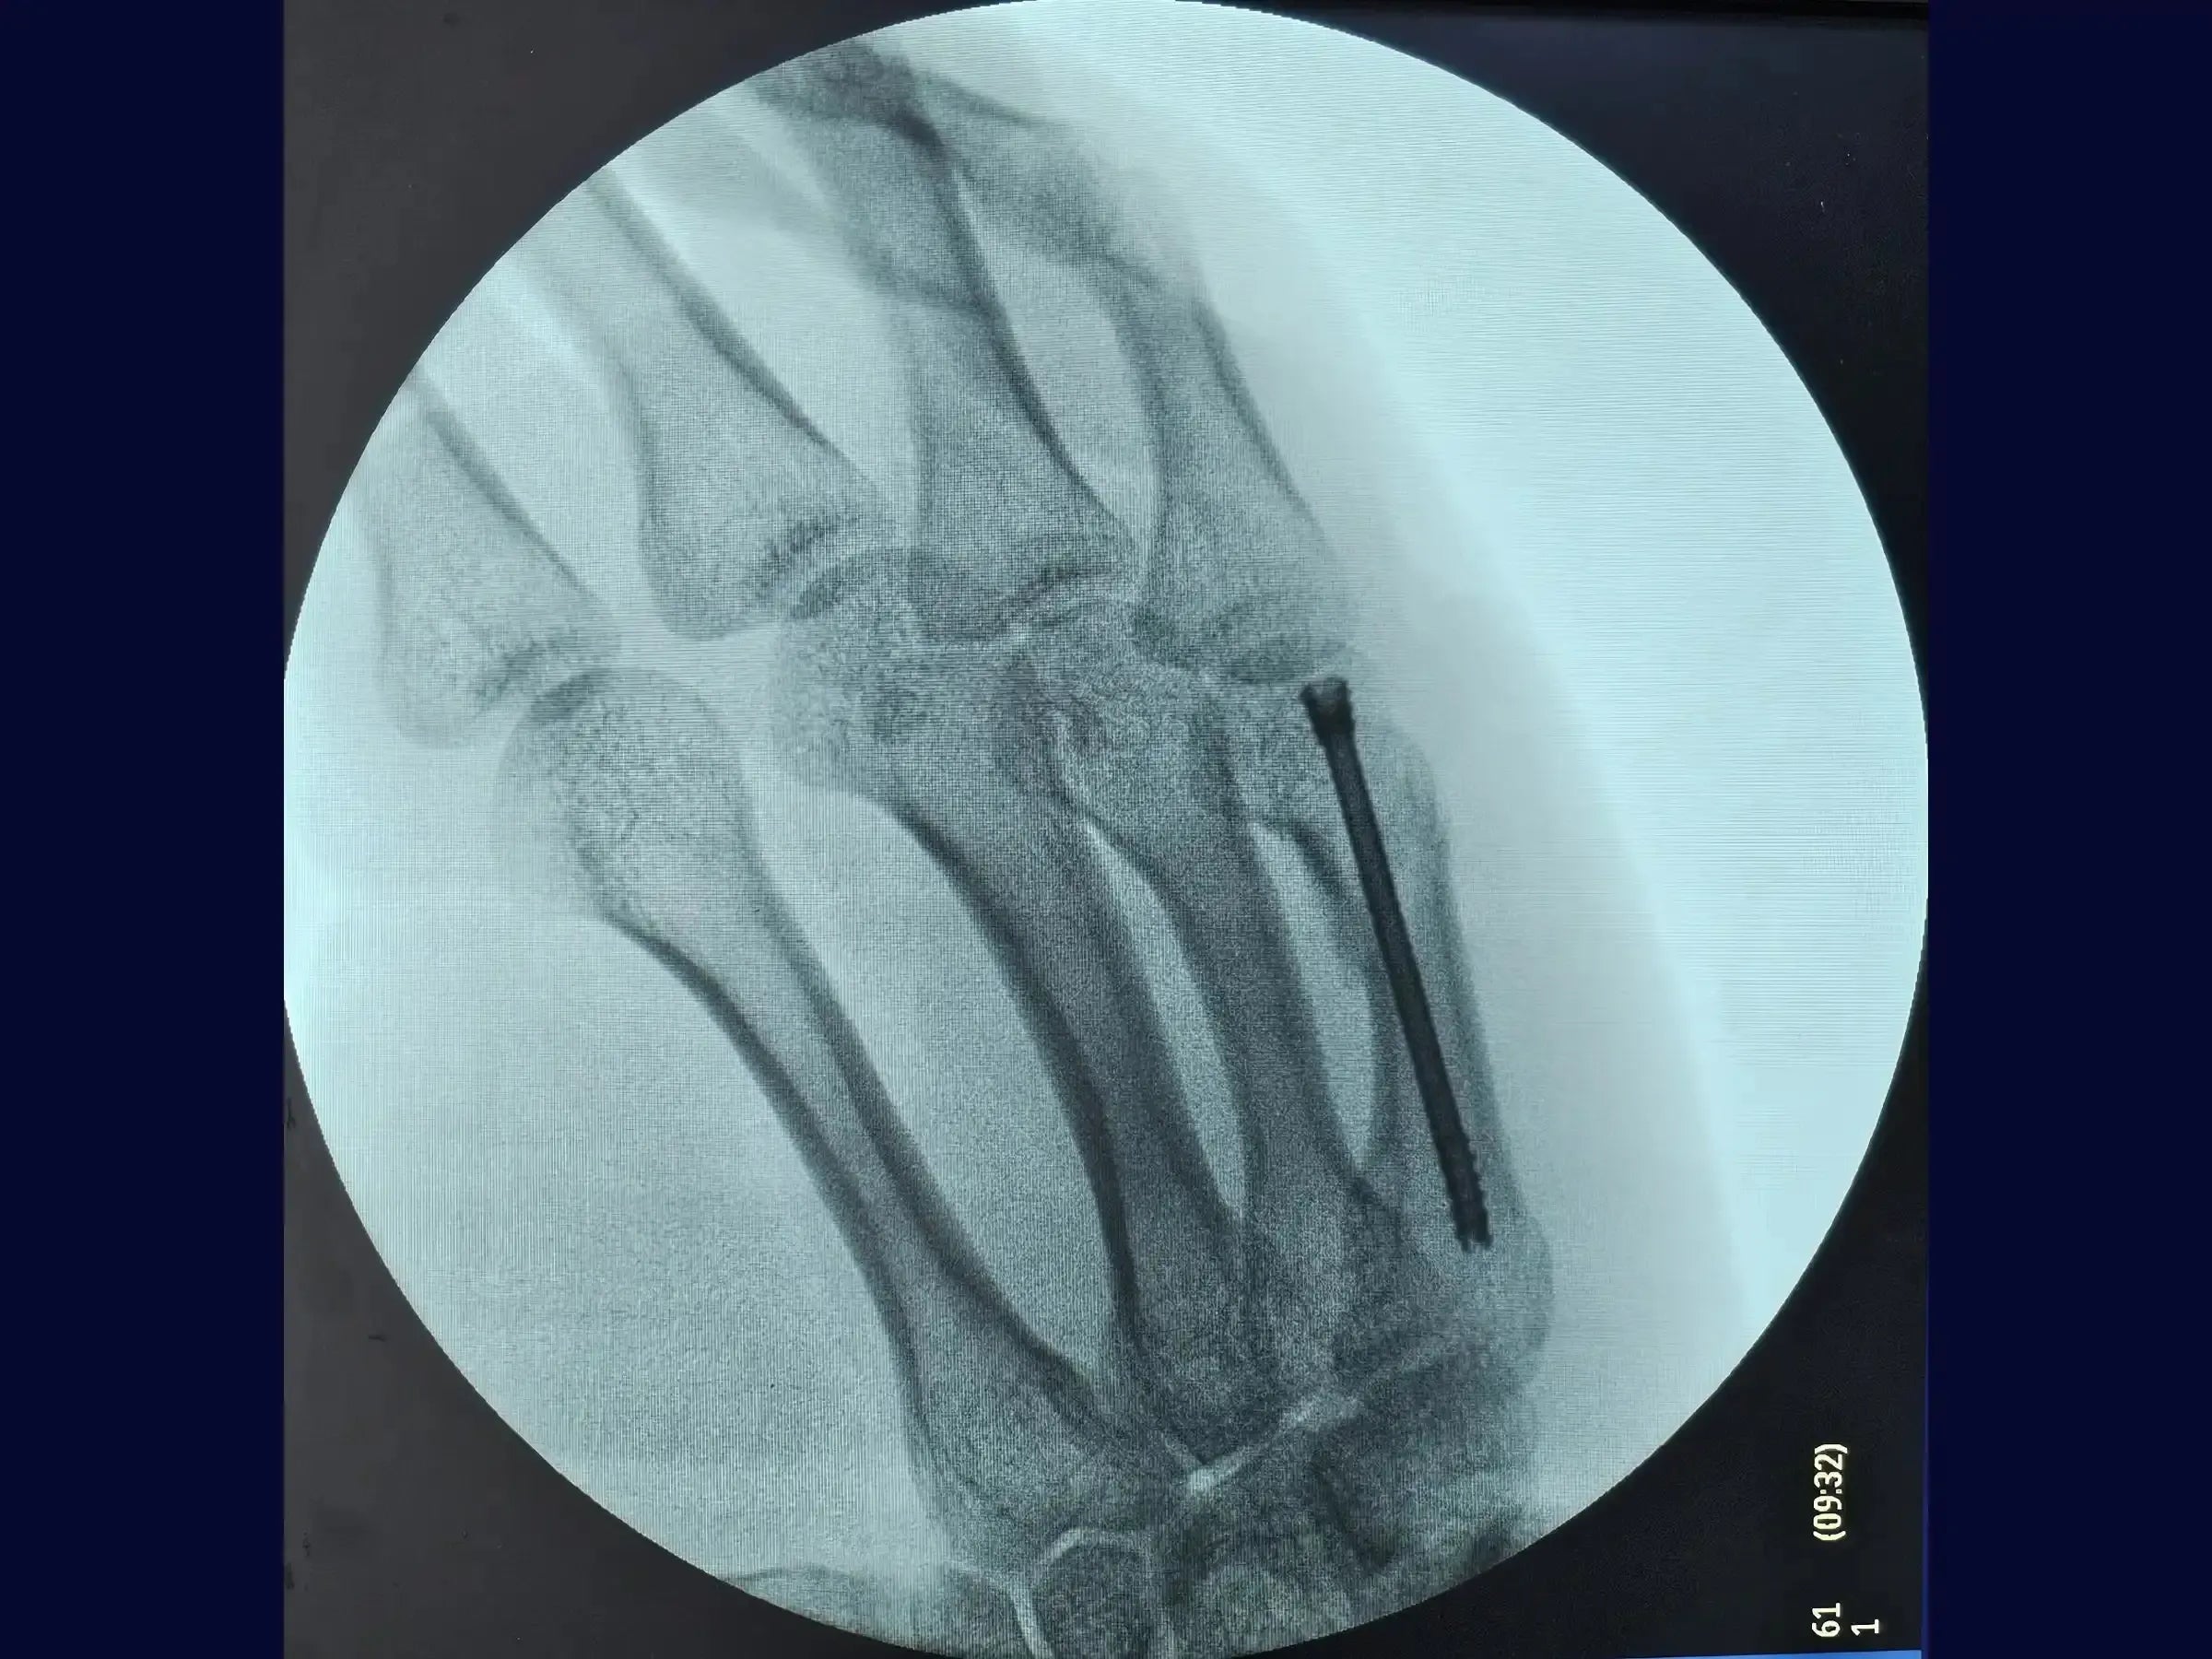

- Inserción de Tornillo de Doble Compresión: Dominar la técnica de inserción del tornillo de doble compresión a través de la guía, siguiendo las pautas establecidas en manuales como el AO.

- Confirmación final y recuperación acelerada: Comprenda los criterios para la confirmación final de la fractura reducida y la colocación del tornillo extraarticular. La técnica mínimamente invasiva garantiza una recuperación muy satisfactoria, evitando incisiones cutáneas extensas y abordajes más agresivos, con un cierre cutáneo realizado con solo dos puntos.